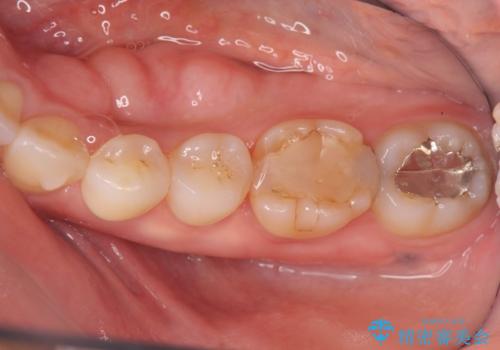

話すのに邪魔な、下顎骨隆起の切除

- 50代女性

- 矯正治療を開始するのに伴い、滑舌を含めた改善を計るために、発音の邪魔となる下顎骨隆起の切除を計画します。